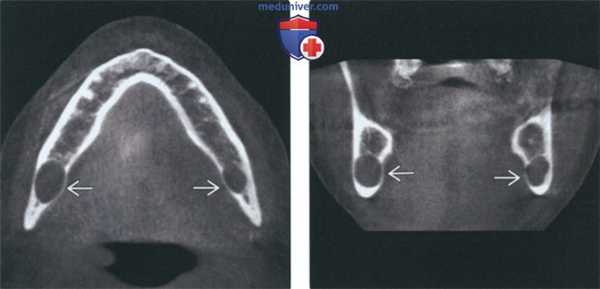

(Слева) МРТ Т1ВИ в аксиальной проекции, пациент, которому ранее проводилось лечение по поводу плоскоклеточного рака носоглотки. Костный мозг в правой ветви нижней челюсти замещен опухолевой тканью, на уровне отверстия нижней челюсти также определяется патологическая ткань, появление которой связано с распространением опухоли по нижнечелюстному нерву. Обратите внимание на нормальный костный мозг левой ветви нижней челюсти, который имеет гиперинтенсивный сигнал.

(Справа) МРТ Т1ВИ в аксиальной проекции, этот же пациент. Периневральное распространение опухоли по нижнечелюстному нерву с облитерацией жировой клетчатки жевательного пространства.